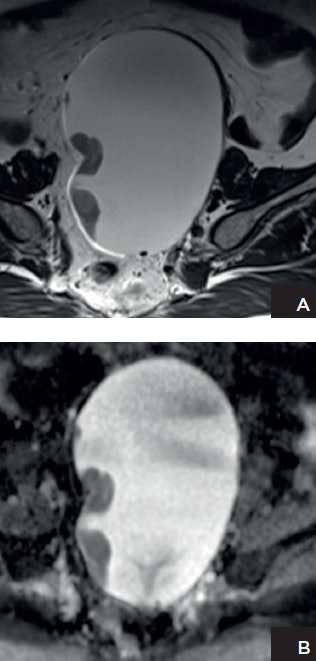

Patient with ovarian cancer. A: Axial T2-weighted high-resolution image shows a left adnexal lesion containing solid components. B: Apparent diffusion coefficient (ADC) map shows marked restricted diffusion in the solid components, highly suggestive of malignancy. Histopathology confirmed the presence of stage 1 high-grade ovarian cancer. Images courtesy of Dr. Evis Sala, PhD.

Patient with ovarian cancer. A: Axial T2-weighted high-resolution image shows a left adnexal lesion containing solid components. B: Apparent diffusion coefficient (ADC) map shows marked restricted diffusion in the solid components, highly suggestive of malignancy. Histopathology confirmed the presence of stage 1 high-grade ovarian cancer. Images courtesy of Dr. Evis Sala, PhD."It is difficult to quantify the percentage of cases for which you would need to repeat or prolong MRI or the cases that could be dismissed or diagnosed after 10 minutes. Successfully incorporating the short protocol depends on the type of practice and patient cohort," he said.